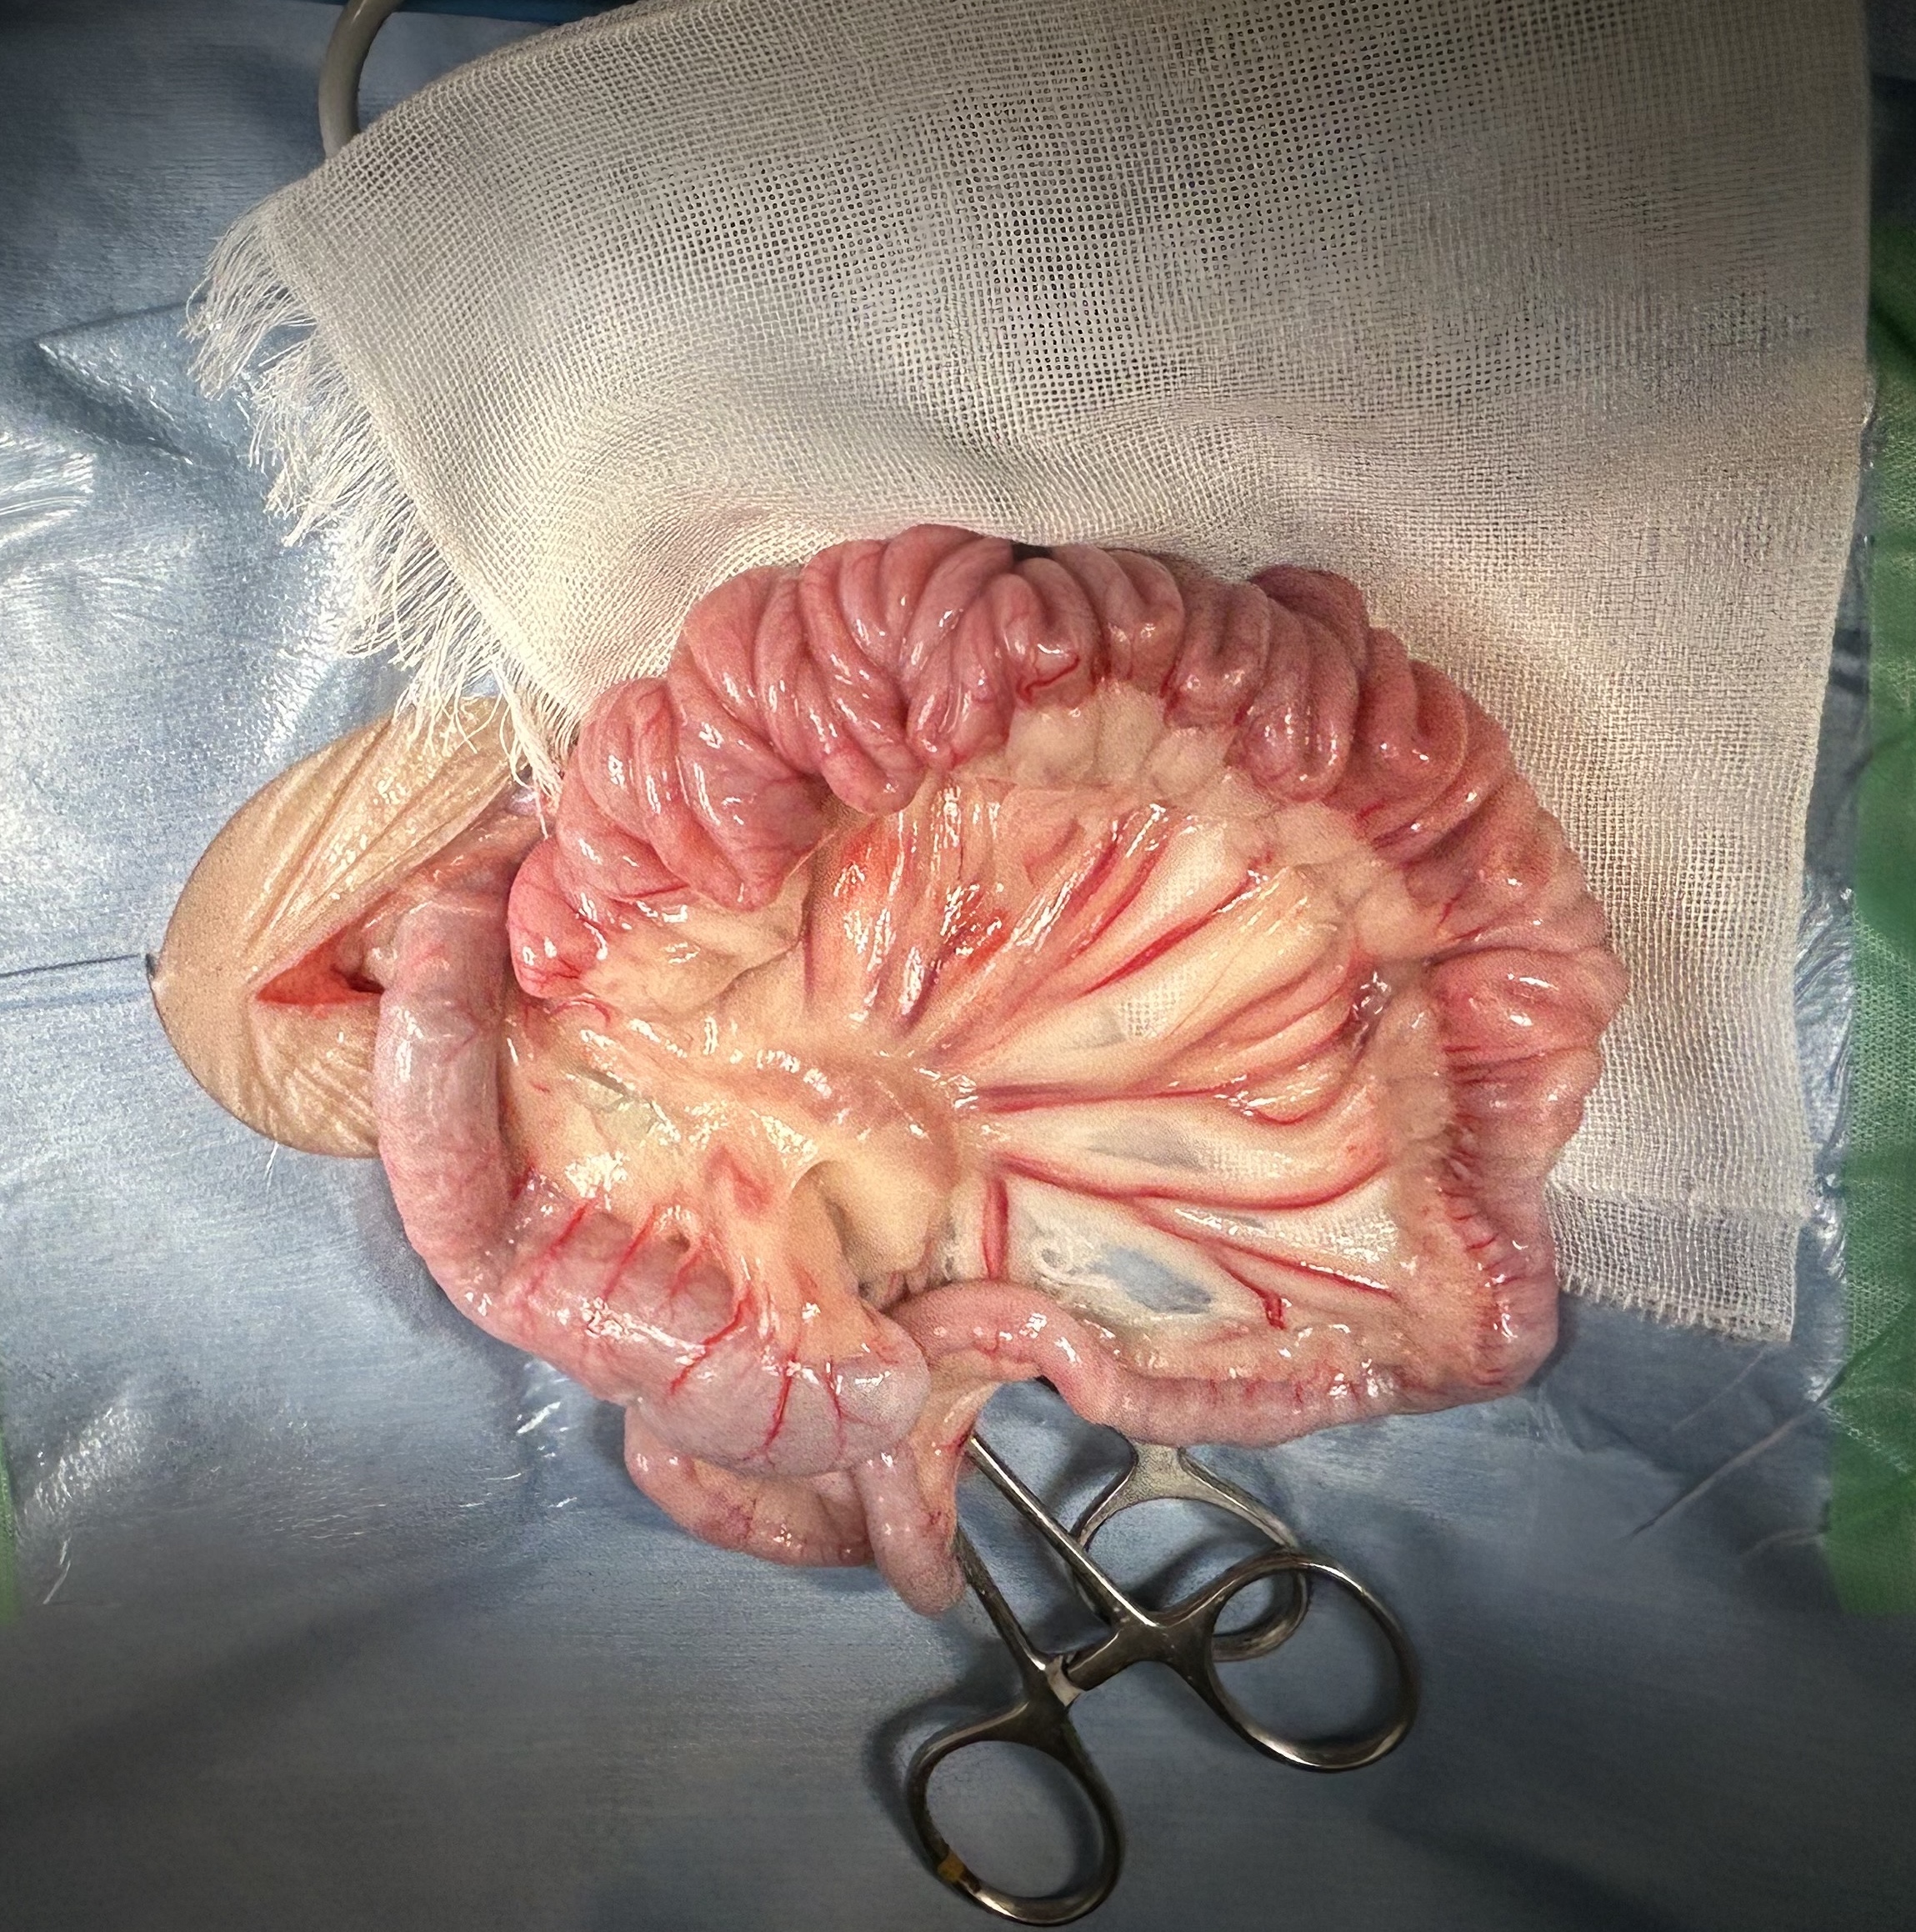

腸内の紐状異物は、動物が誤って糸や紐、ビニールテープなどを誤飲した場合に、腸に引っかかってアコーディオン状に手繰り寄せられる非常に危険な状態です

重度の腸閉塞や腸管が裂け腹膜炎などを引き起こし、通常緊急手術が必要となります

開腹手術にて胃切開し、十二指腸切開にて釣り針についていた糸を摘出した